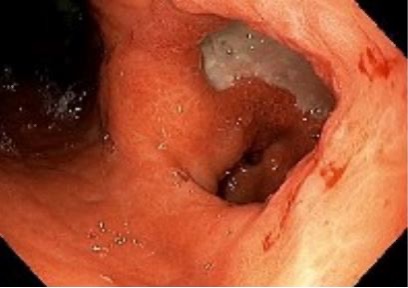

Case Presentation: An 82-year-old woman with a history of cirrhosis (unknown underlying etiology) and intermittent travel to Mexico presented to the emergency room with two weeks of abdominal pain, which included two episodes of hematemesis. She appeared thin, with low muscle mass, and her abdominal examination revealed distension, tenderness, ascites, and a fluid wave. Vitals included a heart rate of 110 beats per minute and a blood pressure of 89/55 mmHg. Laboratory tests revealed leukocytosis (white blood cell count 14.9 K/uL), anemia (hemoglobin 9.9 g/dL), and significantly elevated urea (43 mg/dL) and ferritin (4464 ng/mL). Liver function tests, metabolic panel, and coagulation profile were normal. Paracentesis gram stain and culture, as well as cytology and other fluid studies were within normal limits. CT imaging of the abdomen and pelvis revealed a 5 x 10 x 9 cm multilobulated hyper-enhancing mass in the gastric body/antrum, with erosion into the adjacent transverse colon. An esophagogastroduodenoscopy (EGD) with biopsy confirmed Cytomegalovirus (CMV) gastritis. Notably, the Helicobacter pylori (H. pylori) stain was negative. She was discharged from the hospital medicine service after a one-week admission with a two-week course of oral valganciclovir and a proton pump inhibitor. A repeat EGD three months later showed improvement in gastric erosions, and CT showed an interval decrease in the size of the gastric mass.

Discussion: The differential for abdominal pain and hematemesis is extensive, with bleeding varices a concern in decompensated cirrhosis. Imaging suggested malignancy such as gastric adenocarcinoma, but infectious etiologies, such as tuberculous gastritis, histoplasmosis, CMV and H. pylori, were also considered.CMV, a virus in the herpesvirus family, can reactivate in immunocompromised hosts, leading to gastrointestinal symptoms such as abdominal pain and bleeding. In this patient, CMV infection manifested as an ulcerated exophytic mass in the gastrointestinal tract. The virus can also trigger acute gastric mucosal lesions and lead to chronic inflammation, with the development of pseudotumors. Diagnosis in cases of gastric masses hinges on endoscopic evaluation and histopathology to exclude H. pylori gastritis or malignancy. While both CMV and H. pylori can cause gastritis, their management differs significantly. CMV may improve with proton pump inhibitors alone, while H. pylori requires antibiotics. Endoscopic findings in CMV gastritis, such as punched-out ulcers and necrotic mucosa, are distinctive. Cytomegalic cells with basophilic inclusions (“owl’s eyes”) are highly specific for CMV. In contrast, H. pylori-related ulcers typically exhibit more uniform appearances with chronic changes. Distinguishing between these two gastric conditions is crucial for appropriate treatment. Although serum testing and polymerase chain reaction may suggest CMV, in early infection they may not be reliable and thus biopsy is critical for accurate diagnosis and treatment.